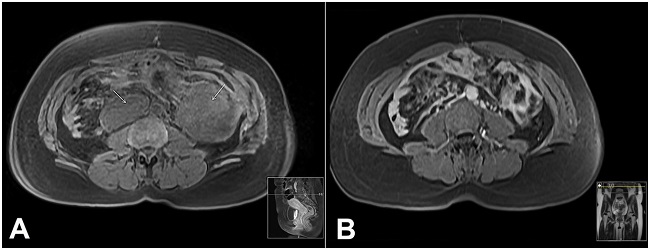

The patient was started on tamoxifen initially with 20 mg/day, increasing up to 40 mg/day, but because of a diagnosis of cholelithiasis it was decreased again to 20 mg/day. However, due to disease progression with the appearance of new lesions (Figure 2A), the chemotherapy regimen with dacarbazine (300 mg/m2) and doxorubicin (20 mg/m2)—administered at day 1, 2, and 3, and repeated every 21 days—was approved by the Institutional Ethics Committee. This regimen was further switched, after eight cycles, to vinorelbine (25 mg/m2) and methotrexate (30 mg/m2) because of the patient’s intolerance (with myelosuppression) and the progression of the pelvic lesion—albeit with the regression of all others. There was a significant response to this last protocol—administered at day 1, 8, and 15, and repeated every 28 days—with dimensional regression of all lesions (Figure 2B) and pain resolution after 14 cycles of chemotherapy.